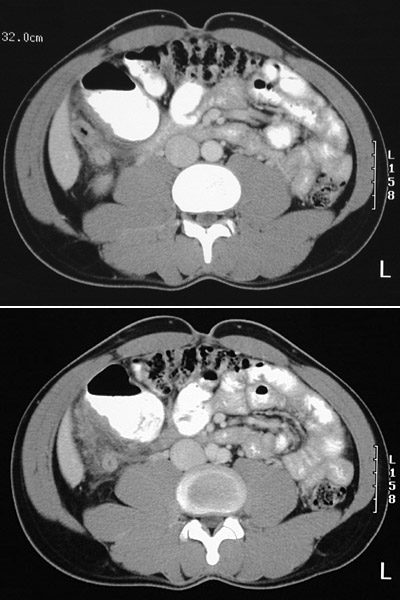

![]() | This abdominal CT scan reveals acute appendicitis with a thickened appendix. This patient had the classic onset of lower abdominal pain that localized over a day to the right lower quadrant, with rebound tenderness on physical examination. A CBC showed a leukocytosis with left shift. There is stranding from inflammation extending to surrounding adipose tissue. |